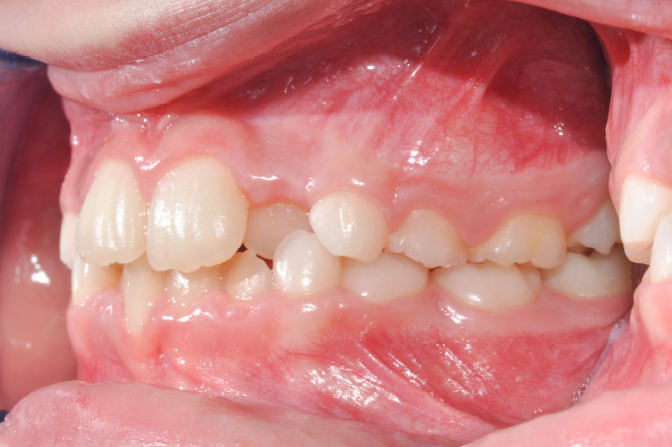

The patient presented with a skeletal Class I relationship and a mesofacial growth pattern, indicating balanced sagittal and vertical skeletal proportions. Dental examination revealed a Class I molar and canine relationship bilaterally. The patient was in the mixed dentition phase. Significant dental crowding was observed in both arches, consistent with a dentoalveolar discrepancy. Midline deviations were present, affecting dental symmetry and occlusal harmony. The maxillary lateral incisors were in crossbite, contributing to anterior transverse discrepancy and functional imbalance.

Periodontal evaluation revealed early signs of periodontal disease, primarily affecting tooth 41. Radiographic assessment demonstrated root convergence of teeth 11 and 21, indicating compromised root parallelism. Overall, the initial presentation was characterized by dentoalveolar crowding, transverse discrepancies, occlusal asymmetries, and early periodontal involvement within an otherwise favorable skeletal framework, requiring a carefully planned orthodontic approach to ensure functional stability and periodontal preservation.